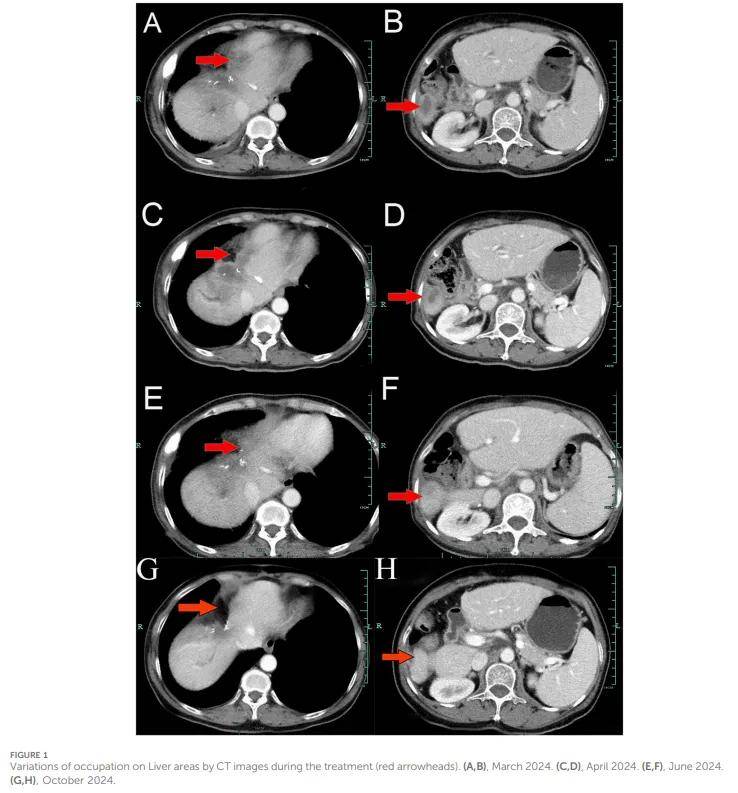

患者女,62 岁,中国人,因右上腹阵发性疼痛近 1 个月,于 2022 年 12 月 24 日入住衢州市人民医院。患者无吸烟、饮酒史,无重大合并症,无癌症家族史。次日,腹部增强计算机断层扫描(CT)显示肝右叶可见一大小约 6.1×4.9 cm的类肿块状低密度影,伴远端肝内胆管轻度扩张。胸部CT及头颅增强磁共振成像(MRI)未见转移征象。随后,患者于 2022 年 12 月 29 日接受扩大解剖性肝中叶切除术(包括IV段、V段、VIII段及尾状叶腔静脉旁部分),联合第一、二肝门血管切除及胆道狭窄重建(右前、后胆管部分切除整形),并行肝十二指肠韧带淋巴结清扫术。手术顺利完成,达到R0切除(切缘阴性)。术后病理及免疫组化检查确诊为中分化胆管癌。免疫组化结果如下:CK7(阳性)、CK19(阳性)、CK20(阳性)、CK18(阳性)、Hepatocyte(阴性)、AFP(阴性)、GPC-3(阴性)、CD34(阴性)、CD10(局灶阳性)、CDX-2(阴性);Ki-67(阳性,60%),PD-L1表达 <1%。下一代测序(NGS)结果如下:BRCA1(外显子10,p.Q1111fs,变异丰度:19.7%)、PALB2(外显子9,p.E956*,变异丰度:19.8%)及TP53(外显子5,p.Q165fs,变异丰度:33.6%)。根据美国癌症联合委员会(AJCC)第 8 版分期标准,诊断为胆管癌,分期为T4NxM0。患者于 2023 年 1 月 28 日接受首次术后免疫联合化疗,方案为替雷利珠单抗(静脉注射 200 mg)+吉西他滨(第 1 天 800 mg/第 8 天 600 mg,静脉注射)+奥沙利铂(第 1 天100 mg,静脉注射)。然而,由于出现严重骨髓抑制,患者随后接受了 4 个周期的替雷利珠单抗(第 1 天静脉注射200 mg,每 14 天为 1 周期)、替吉奥(第 2-15 天静脉注射 400 mg,每 14 天为 1 周期)及奥沙利铂(第 1 天静脉注射 100 mg,每 14 天为 1 周期)治疗。因右侧胸痛 1 周,患者于 2023 年 8 月 8 日复查胸部CT,结果显示右侧第 7 肋骨增厚、密度增高,伴周围软组织肿胀。患者随后接受该区域立体定向体部放疗(SBRT),处方剂量 35 Gy/5 次(每次7 Gy)。2023 年 11 月 11 日腹部CT显示肝内胆管轻度扩张,随后患者接受放疗方案 50 Gy/2 Gy/25 次。因频繁腰痛,患者于 2024 年 1 月 23 日接受腰椎MRI检查,结果显示胸1、胸6-11及腰椎多发斑片状影。随后,患者接受单剂量替雷利珠单抗(200 mg)治疗,并后续接受立体定向体部放疗,方案为 30 Gy/10次(每次 3 Gy)。不幸的是,2024 年 3 月 15 日腹部CT显示多发新增转移灶(图1A、B)。鉴于NGS结果、患者ECOG体力状况评分 2 分,以及其强烈希望继续积极治疗的意愿,启动了奥拉帕利挽救治疗,该药为口服BRCA靶向PARP抑制剂,剂量为 150 mg每日 2 次。随后于 2024 年 4 月 30 日(图1C、D)及 2024 年 6 月 4 日(图1E、F)进行的腹部CT检查显示肿瘤缩小,根据RECIST 1.1标准达到部分缓解(PR)。患者维持PR状态,无影像学进展,直至 2024 年 10 月因经济原因停止奥拉帕利治疗并转为中药治疗(图1G、H)。重要的是,患者对奥拉帕利耐受性良好,整个治疗过程中未报告治疗相关不良事件。同时,奥拉帕利治疗期间观察到肿瘤标志物CA199和CA153显著下降(图2),患者体力状况亦有所改善。不幸的是,患者于 2024 年 12 月因肺炎继发II型呼吸衰竭去世。诊断过程、治疗方案及靶病灶变化的总结见图3。

▲图1 治疗期间的肝占位CT变化